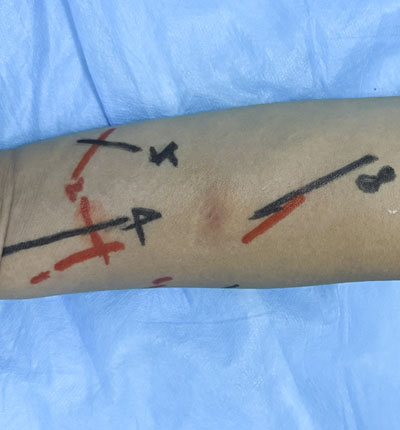

術前定位